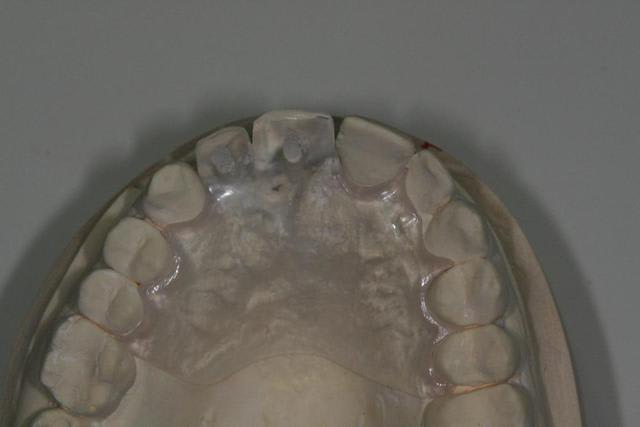

Bon ben j'ai implanté avant d'avoir refait la 21. Du coup j'ai mésialé la pose de 11 pour compenser la distalisation de 21.

Au final je n'ai pas fait de greffe osseuse... et j'ai réalisé une technique de rouleau sur 11-12 mais je reste un peu court à mon goût.

J'ai mis en place des transitoires sur 11-12-21 pour temporiser 3 mois pour voir la maturation des tissus mous.

Je réaliserai dans un second temps des piliers procera.

Je mets quelques photos de la patiente au cab et du prothèsiste d'Epinal.

La vraie difficulté a été de retrouver le milieu incisif pour déterminer la position des implants.